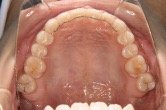

(図4,5矢印)この部分に付着したプラークはむし歯、歯周病両方の原因になるため優先的にブラッシングによる清掃が必要です。

図4マルチブラケット装置(唇側)

図5マルチブラケット装置(舌側)